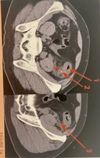

Diagnostique ? | Légender flèches rouges

1) Épaissement pariétal sténosant colon sigmoide 2) Infiltration graisse péri sigmoidienne 3) Diverticule sigmoidien avec infiltration graisse adjacente